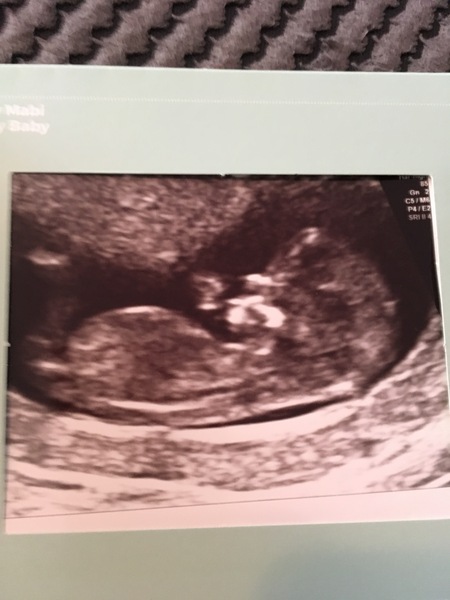

All ok at the scan thankfully! So relieved again. Baby was wriggling away moved my date a day forward so official due date is the 5th April.

Thread no.2 for babies due April 2018

What a lovely little pic! Has anyone thought about the nub theory with their scans?